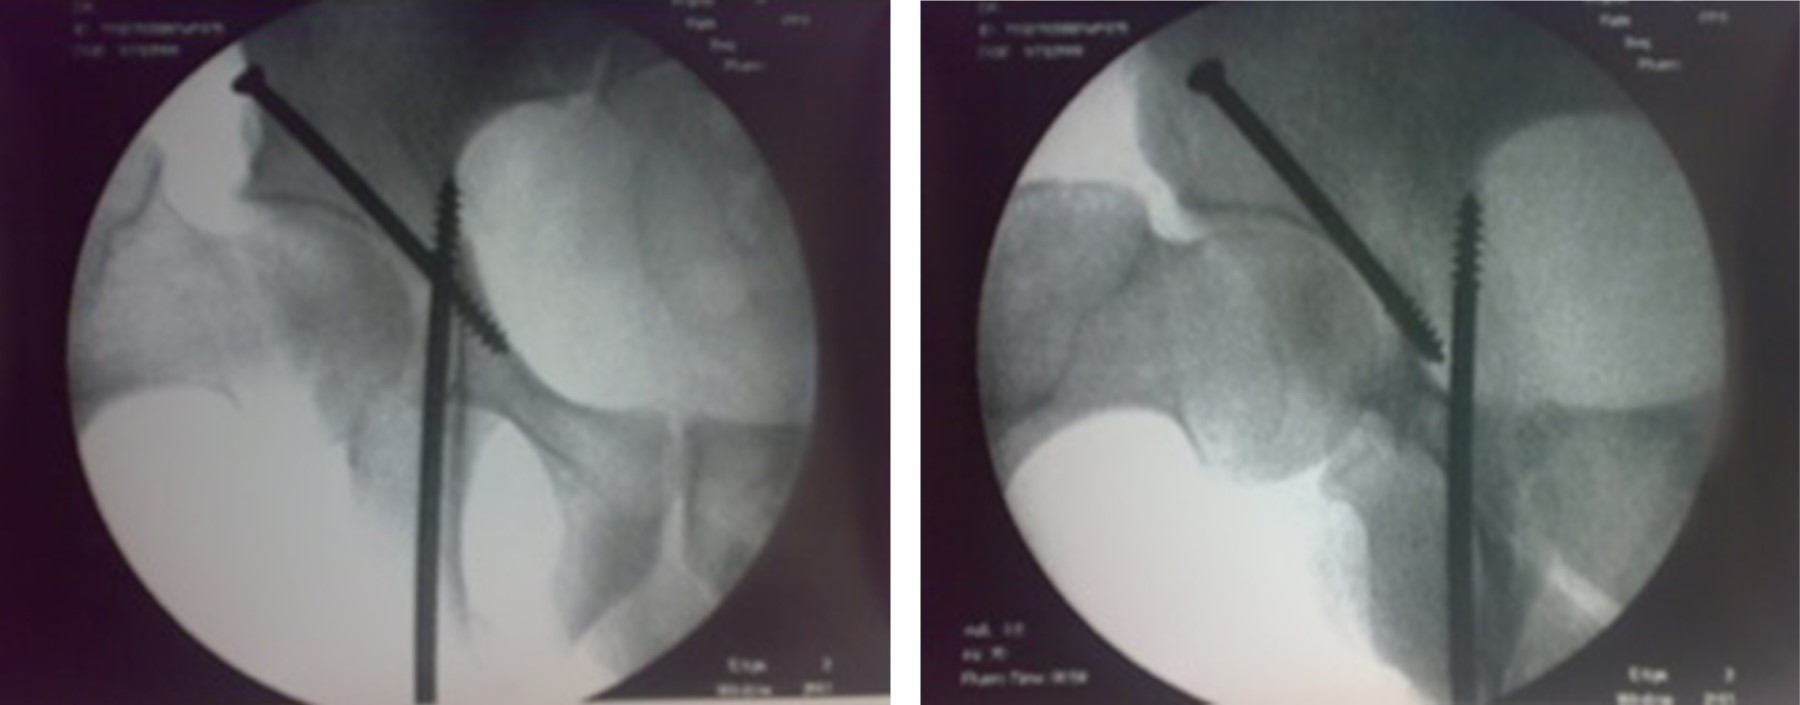

El abordaje percutáneo se asocia con menos complicaciones que las técnicas abiertas, ya que ofrece un tiempo quirúrgico más corto, reduce los peligros relacionados con la exposición quirúrgica, disminuye la pérdida de sangre, existe menor lesión de los tejidos blandos y se asocia con disminución de la estancia intrahospitalaria. Los planos de los tejidos blandos permanecen sin dañarse, lo que posteriormente facilitaría la artroplastia total de cadera en caso de ser necesario.2,3 Sin embargo, la geometría acetabular hace que la inserción percutánea de tornillos sea un procedimiento difícil (Figuras 2 y 3).4

Figura 2

Figura 3